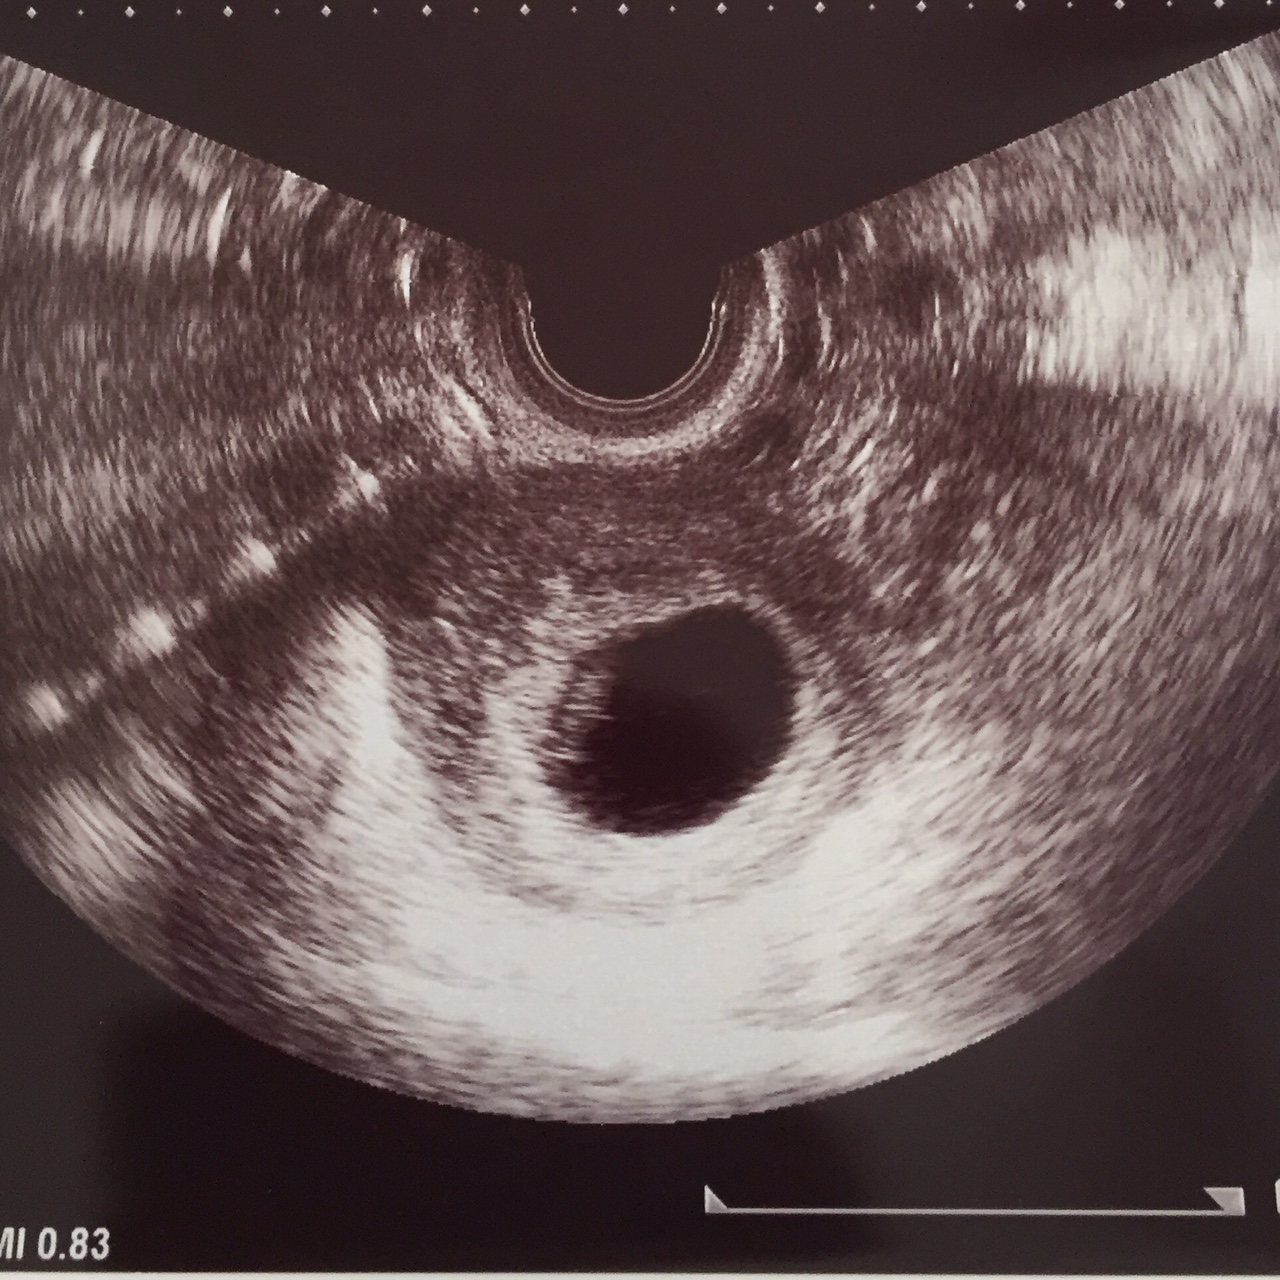

最後にエコー写真を載せます。

大きさは不明ですが。胎嚢が3〜4センチくらい。

赤ちゃんは1〜2センチくらいです。